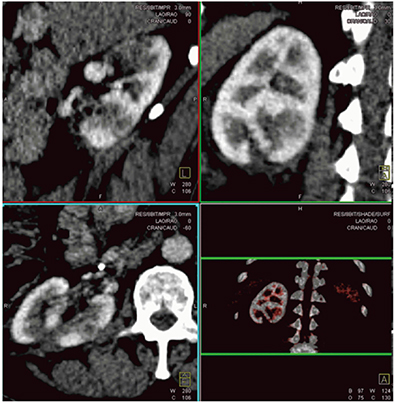

Case5は,Dynamic 4D Shuttle Mode Perfusion CTが腫瘍検出に有用であった神経内分泌腫瘍の転移例であるが,単純CTおよびMRIではいずれも陰性だった。Dynamic 4D Shuttle Mode Perfusion CTでは,シネイメージを確認すると,撮影開始の3.5秒後のわずかの時間に腫瘍濃染が描出されていた。このように,本手法は治療応答性の評価はもとより,腫瘍検出や肝細胞がんの診断にも有用である(図9)。

また,治療効果を評価するツールとしてもDynamic 4D Shuttle Mode Perfusion CTは有用である。Case6は血管筋脂肪腫である。術前の4D-CTで最適な時相を選択することで,静脈系と動脈系を正確に区別することができる(図10)。

図9 Case5:神経内分泌腫瘍の転移例のDynamic 4D Shuttle Mode Perfusion画像(70kV)

図10 Case6:血管筋脂肪腫の術前4D-CT画像